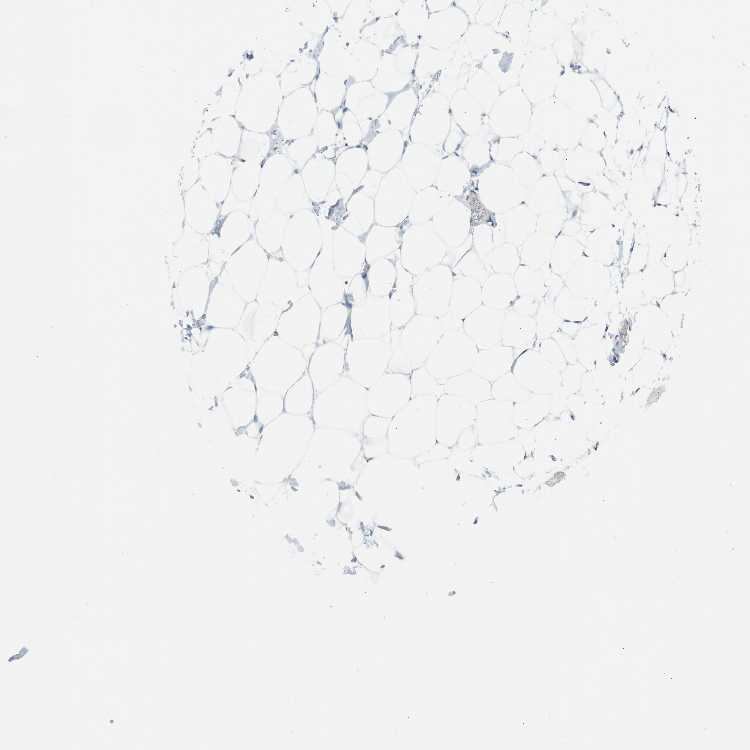

ADIPOSE TISSUE - Antibody stainingi

Antibody staining in the annotated cell types in the current human tissue is reported as not detected, low, medium, or high, based on conventional immunohistochemistry profiling in selected tissues. This score is based on the combination of the staining intensity and fraction of stained cells.

Each image is clickable and will lead to virtual microscopy that enables deeper exploration of all samples and also displays staining intensity scores, fraction scores and subcellular localization as well as patient and tissue information for each sample.

Antibody HPA003980Antibody CAB007772

Adipocytes Not detectedNot detected